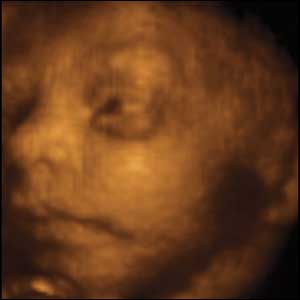

24 week unborn baby

Here is a picture of an unborn baby at 24 weeks

Babies are killed at this age every day. Often by D&E.

sonogram at just 24 weeks